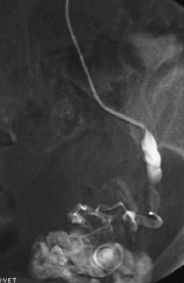

Radiología Linfoma epidural primario sin afectación vertebral en un paciente VIH positivo

Linfoma epidural primario sin afectación vertebral en un paciente VIH positivo

Primary epidural lymphoma without vertebral involvement in a HIV-positive patient